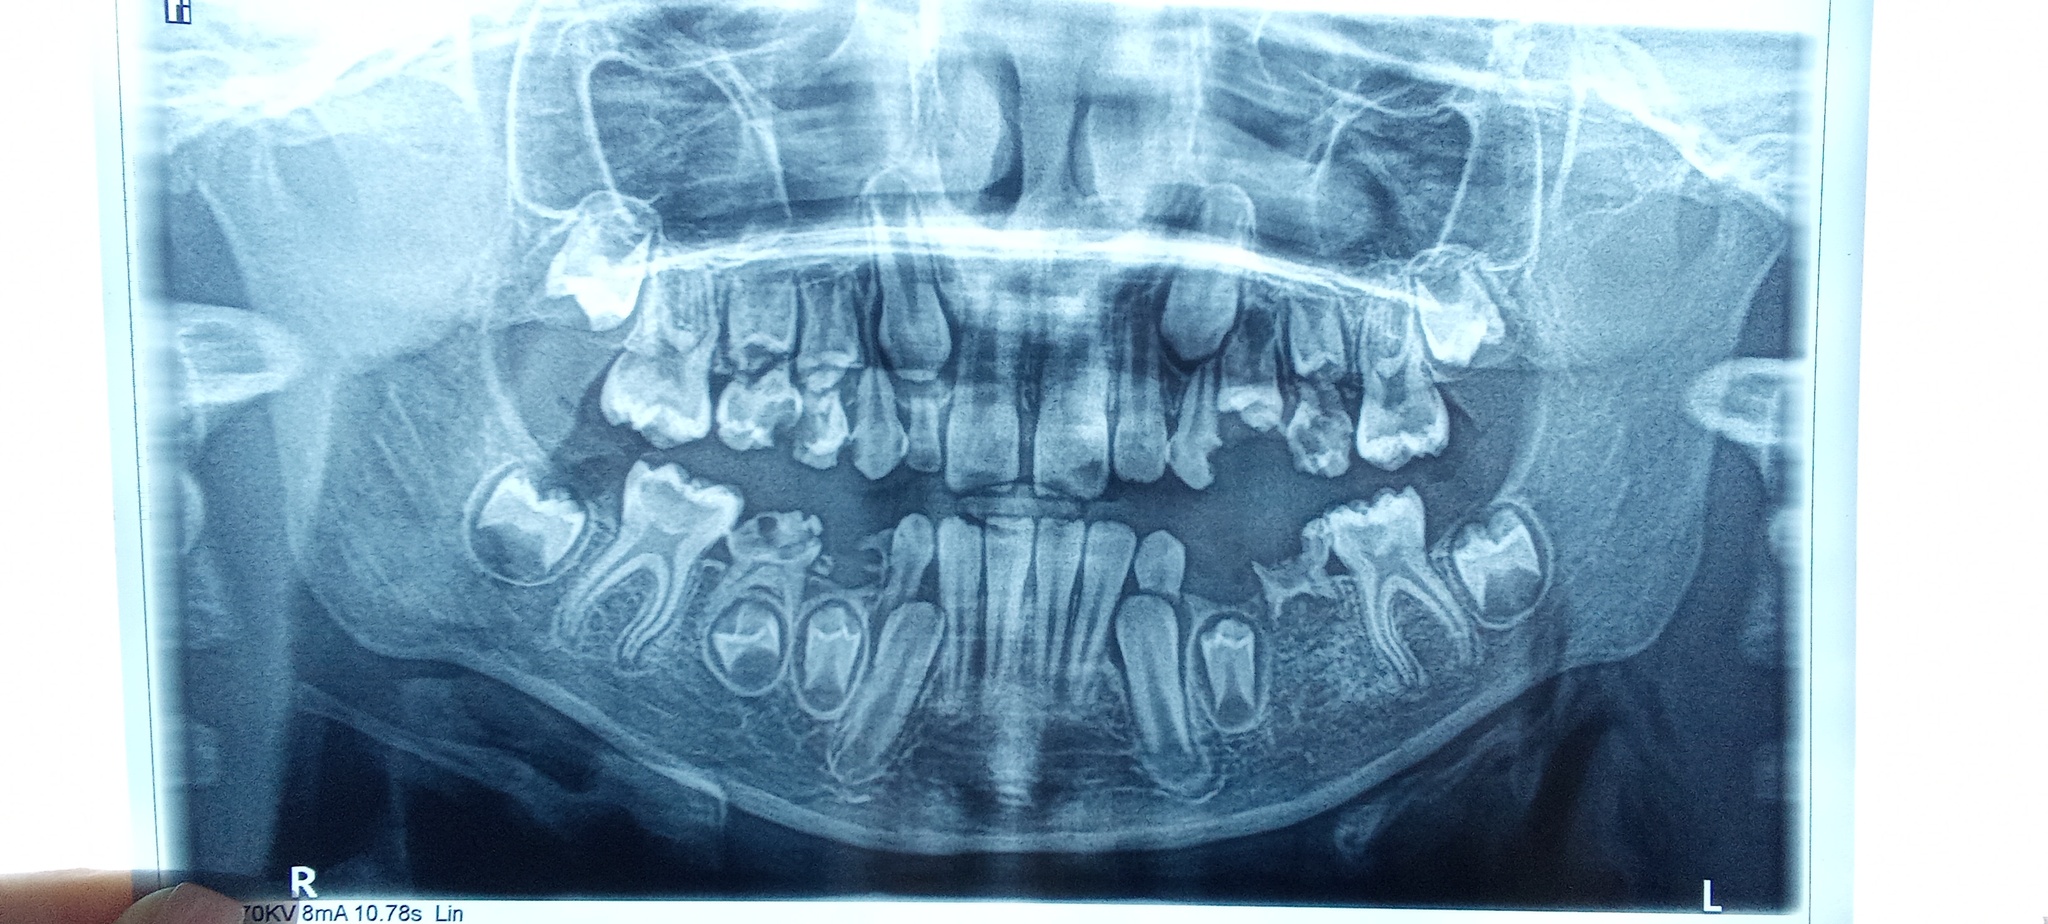

Poorbick Стоматология Зубки. Совет 1 год назад Стоматологи, нужен ваш консультация. Снимок сделан на днях. Справа снизу одного зуба нет? Будет ли он [моё] Стоматология Зубы Дети Совет Длиннопост Ещё 0